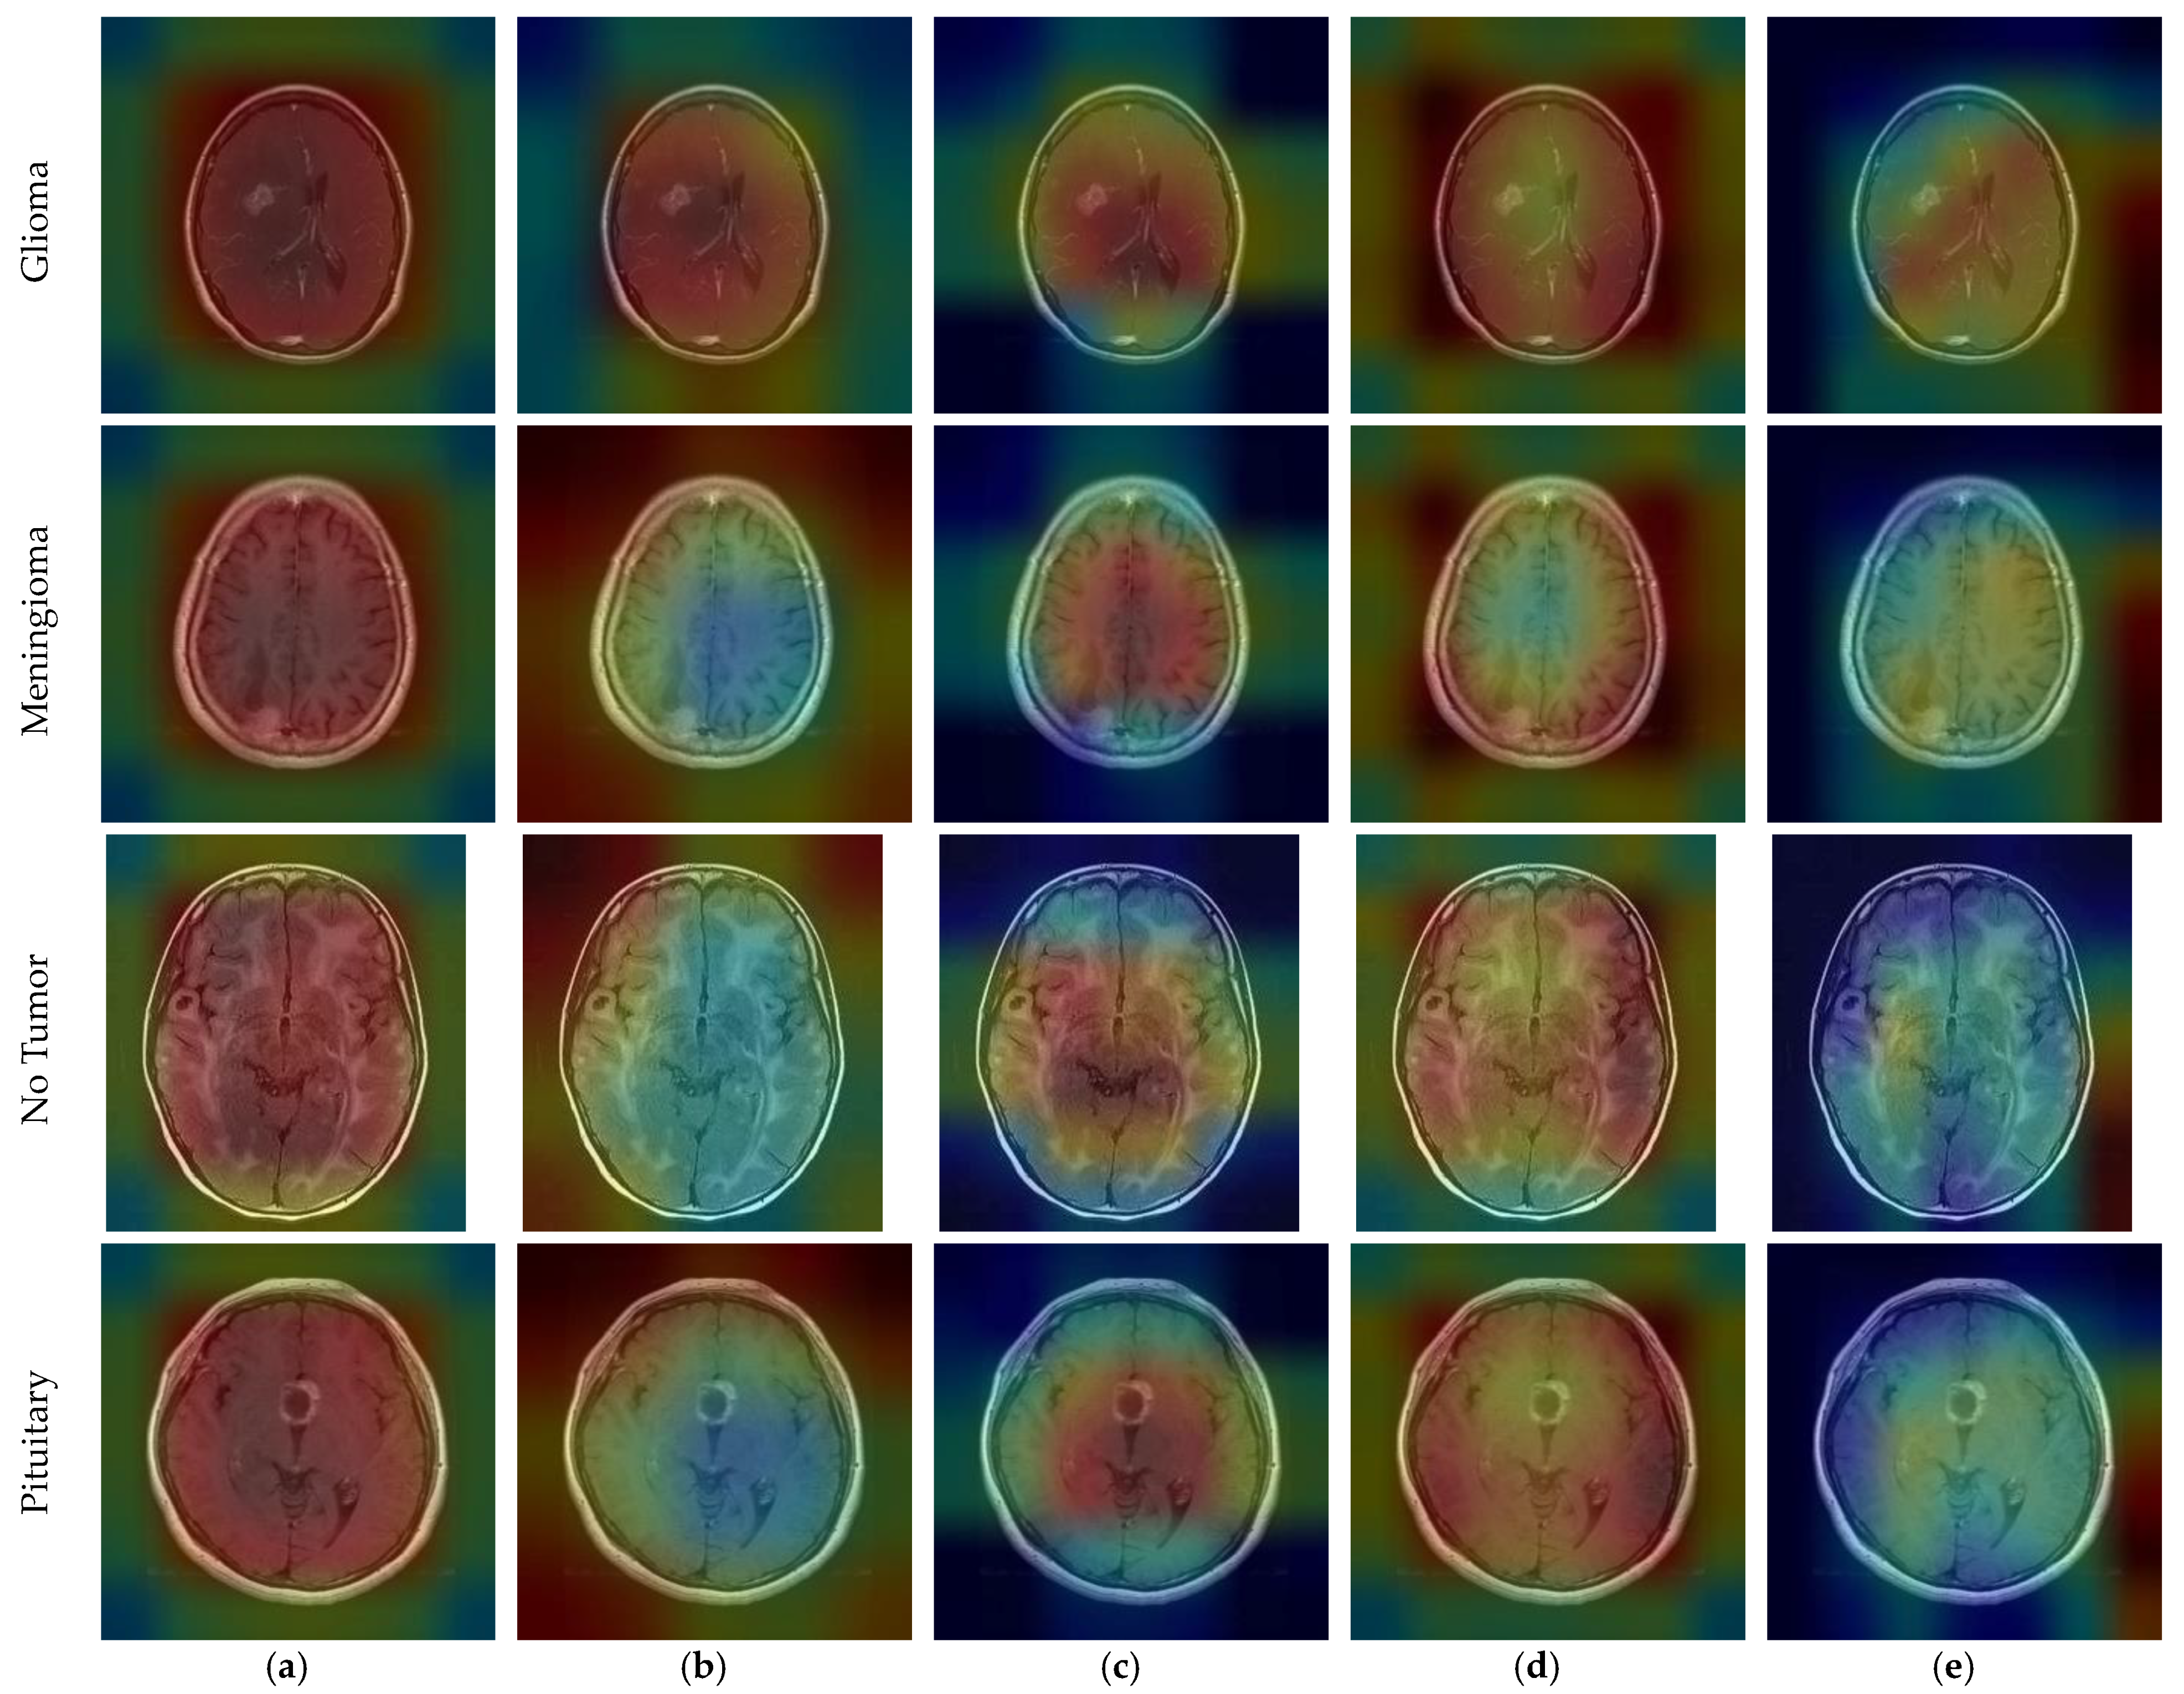

CNN outputs visualized on a heat map with Grad-CAM for Dataset 1, Dataset 2, and Dataset 3 are represented in Figure 10, Figure 11 and Figure 12, respectively. The original images are overlaid with a color spectrum ranging from blue to red, where the red regions indicate the dominant focus during model predictions. The sample images in Figure 1 were used as the original images in the Grad-CAM application. Grad-CAM analyses of the models in the ensemble framework are presented for three data sets. Figure 10 shows that while all models focus on the brain, different models may focus on different regions of the same MRI image. This trend also helps to increase feature diversity. This can be considered an indicator of better performance with ensemble learning.

Figure 10.

CNN outputs visualized on a heat map with Grad-CAM for Dataset 1: (a) DenseNet121, (b) DenseNet201, (c) EfficientNetV2S, (d) ResNet50, and (e) ResNet101.